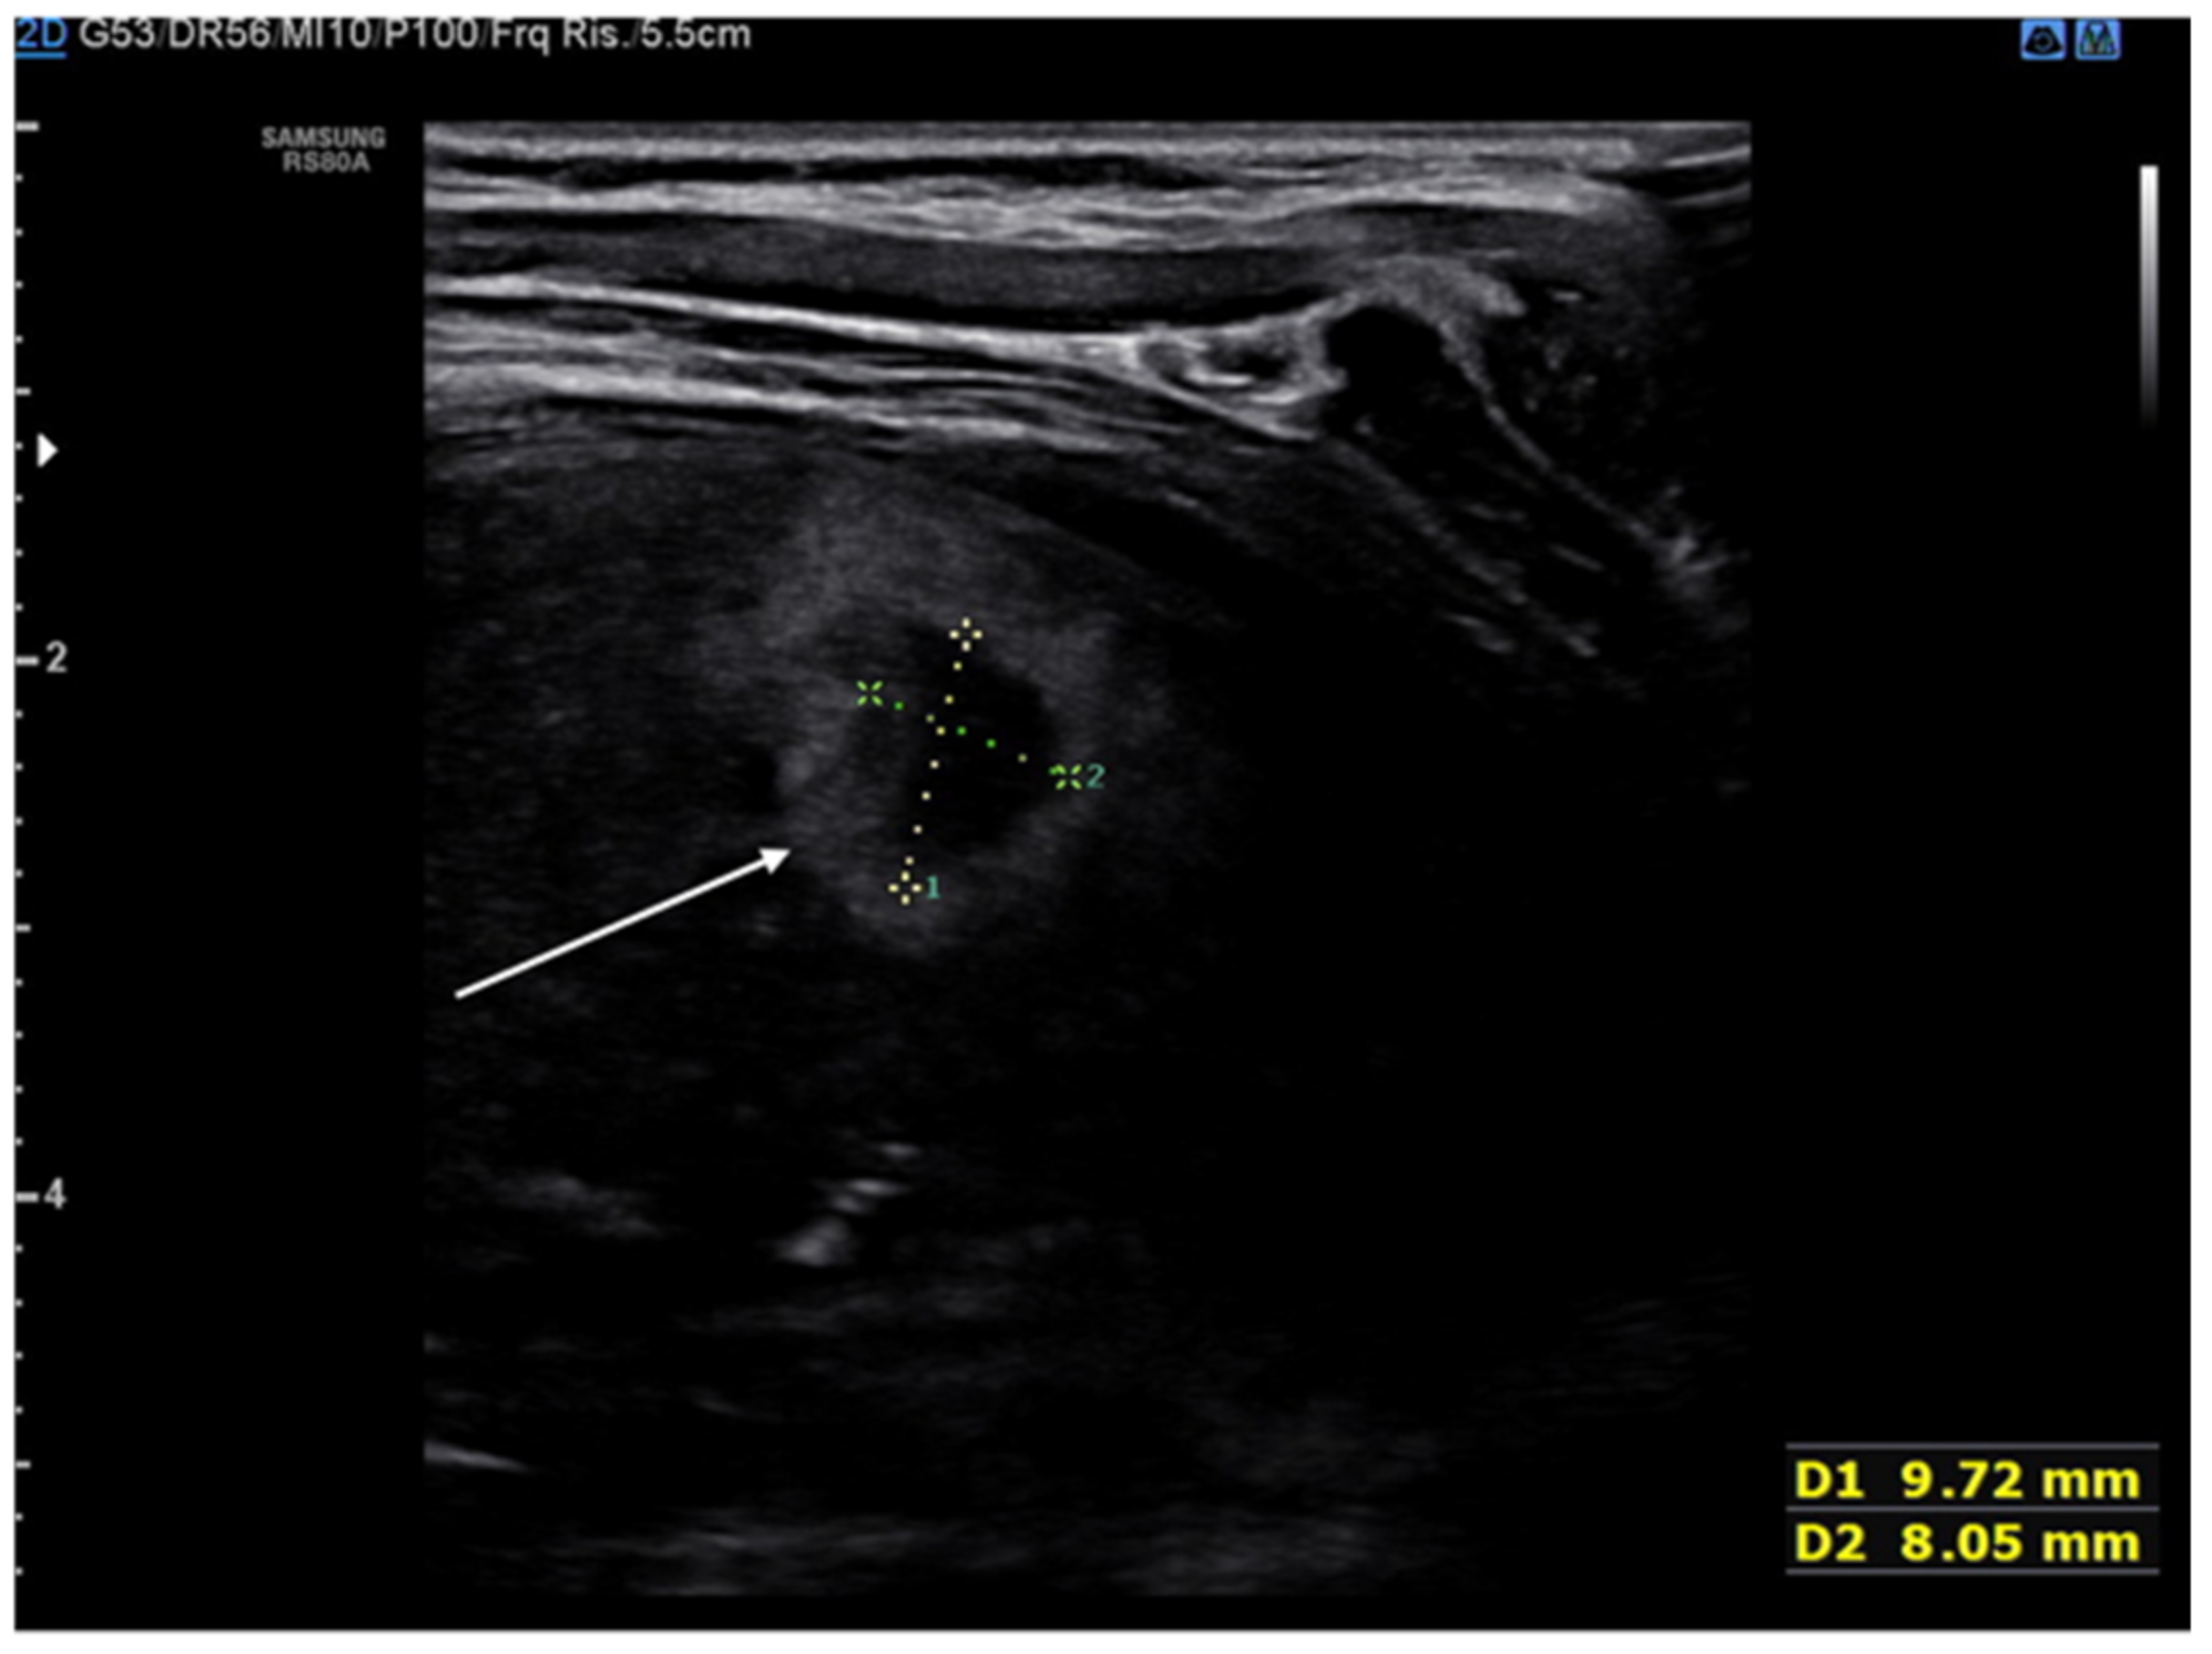

The lung abscess appears as a well-demarcated capsular structure surrounding a hypoechoic core without internal vascularity on color Doppler (Figure 11). Furthermore, it is possible to distinguish lung abscess from pyopneumothorax through the presence of all four specific signs: air-fluid level, synchronous movement of air-fluid levels with breaths, loss of gliding sign above the air-fluid level and the suspended microbubble sign (punctate hyperechoic pinpoints with shadows that move more or less randomly with respiratory movement within the pleural effusion) [56,57].

Figure 11.

Hypoechogenic capsule lesion with irregular, hyperechogenic edges suggestive of lung abscess (white arrow).